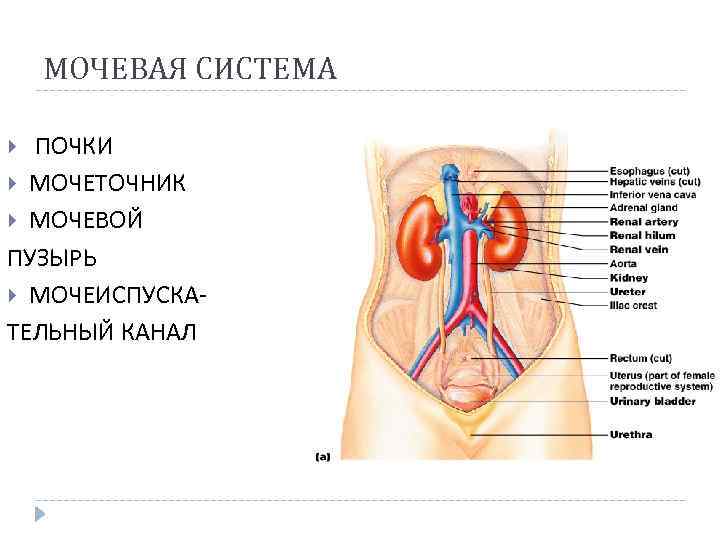

МОЧЕВАЯ СИСТЕМА ПОЧКИ МОЧЕТОЧНИК МОЧЕВОЙ ПУЗЫРЬ МОЧЕИСПУСКАТЕЛЬНЫЙ КАНАЛ

МОЧЕВАЯ СИСТЕМА ПОЧКИ МОЧЕТОЧНИК МОЧЕВОЙ ПУЗЫРЬ МОЧЕИСПУСКАТЕЛЬНЫЙ КАНАЛ